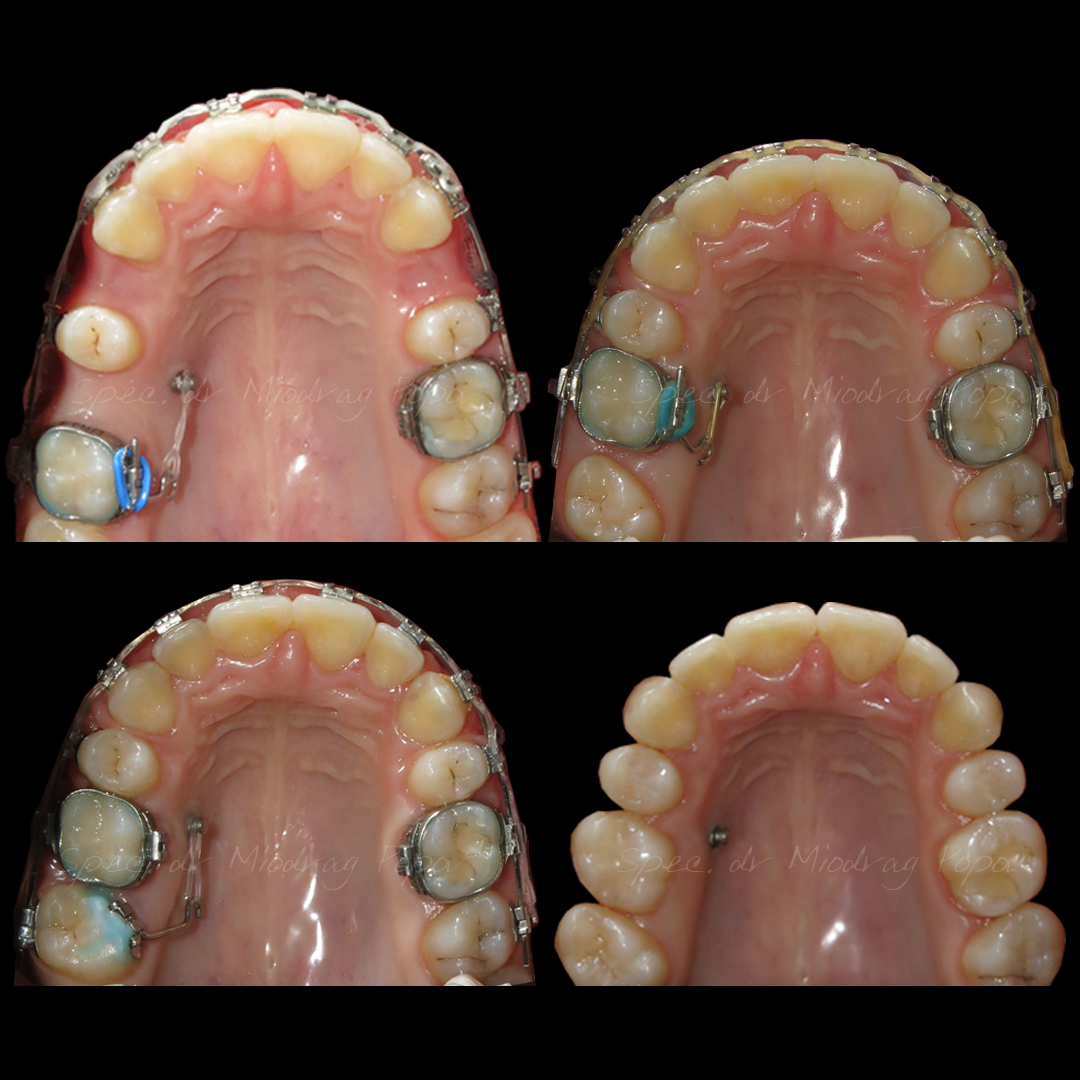

Slučaj ortodontske terapije II klase s vađenjem gornjih prvih predkutnjaka.

Na početku terapije, pacijentkinja je već imala izvađen gornji prvi kutnjak.

Tokom tretmana, svi prostori su zatvoreni, a profil lica transformisan.